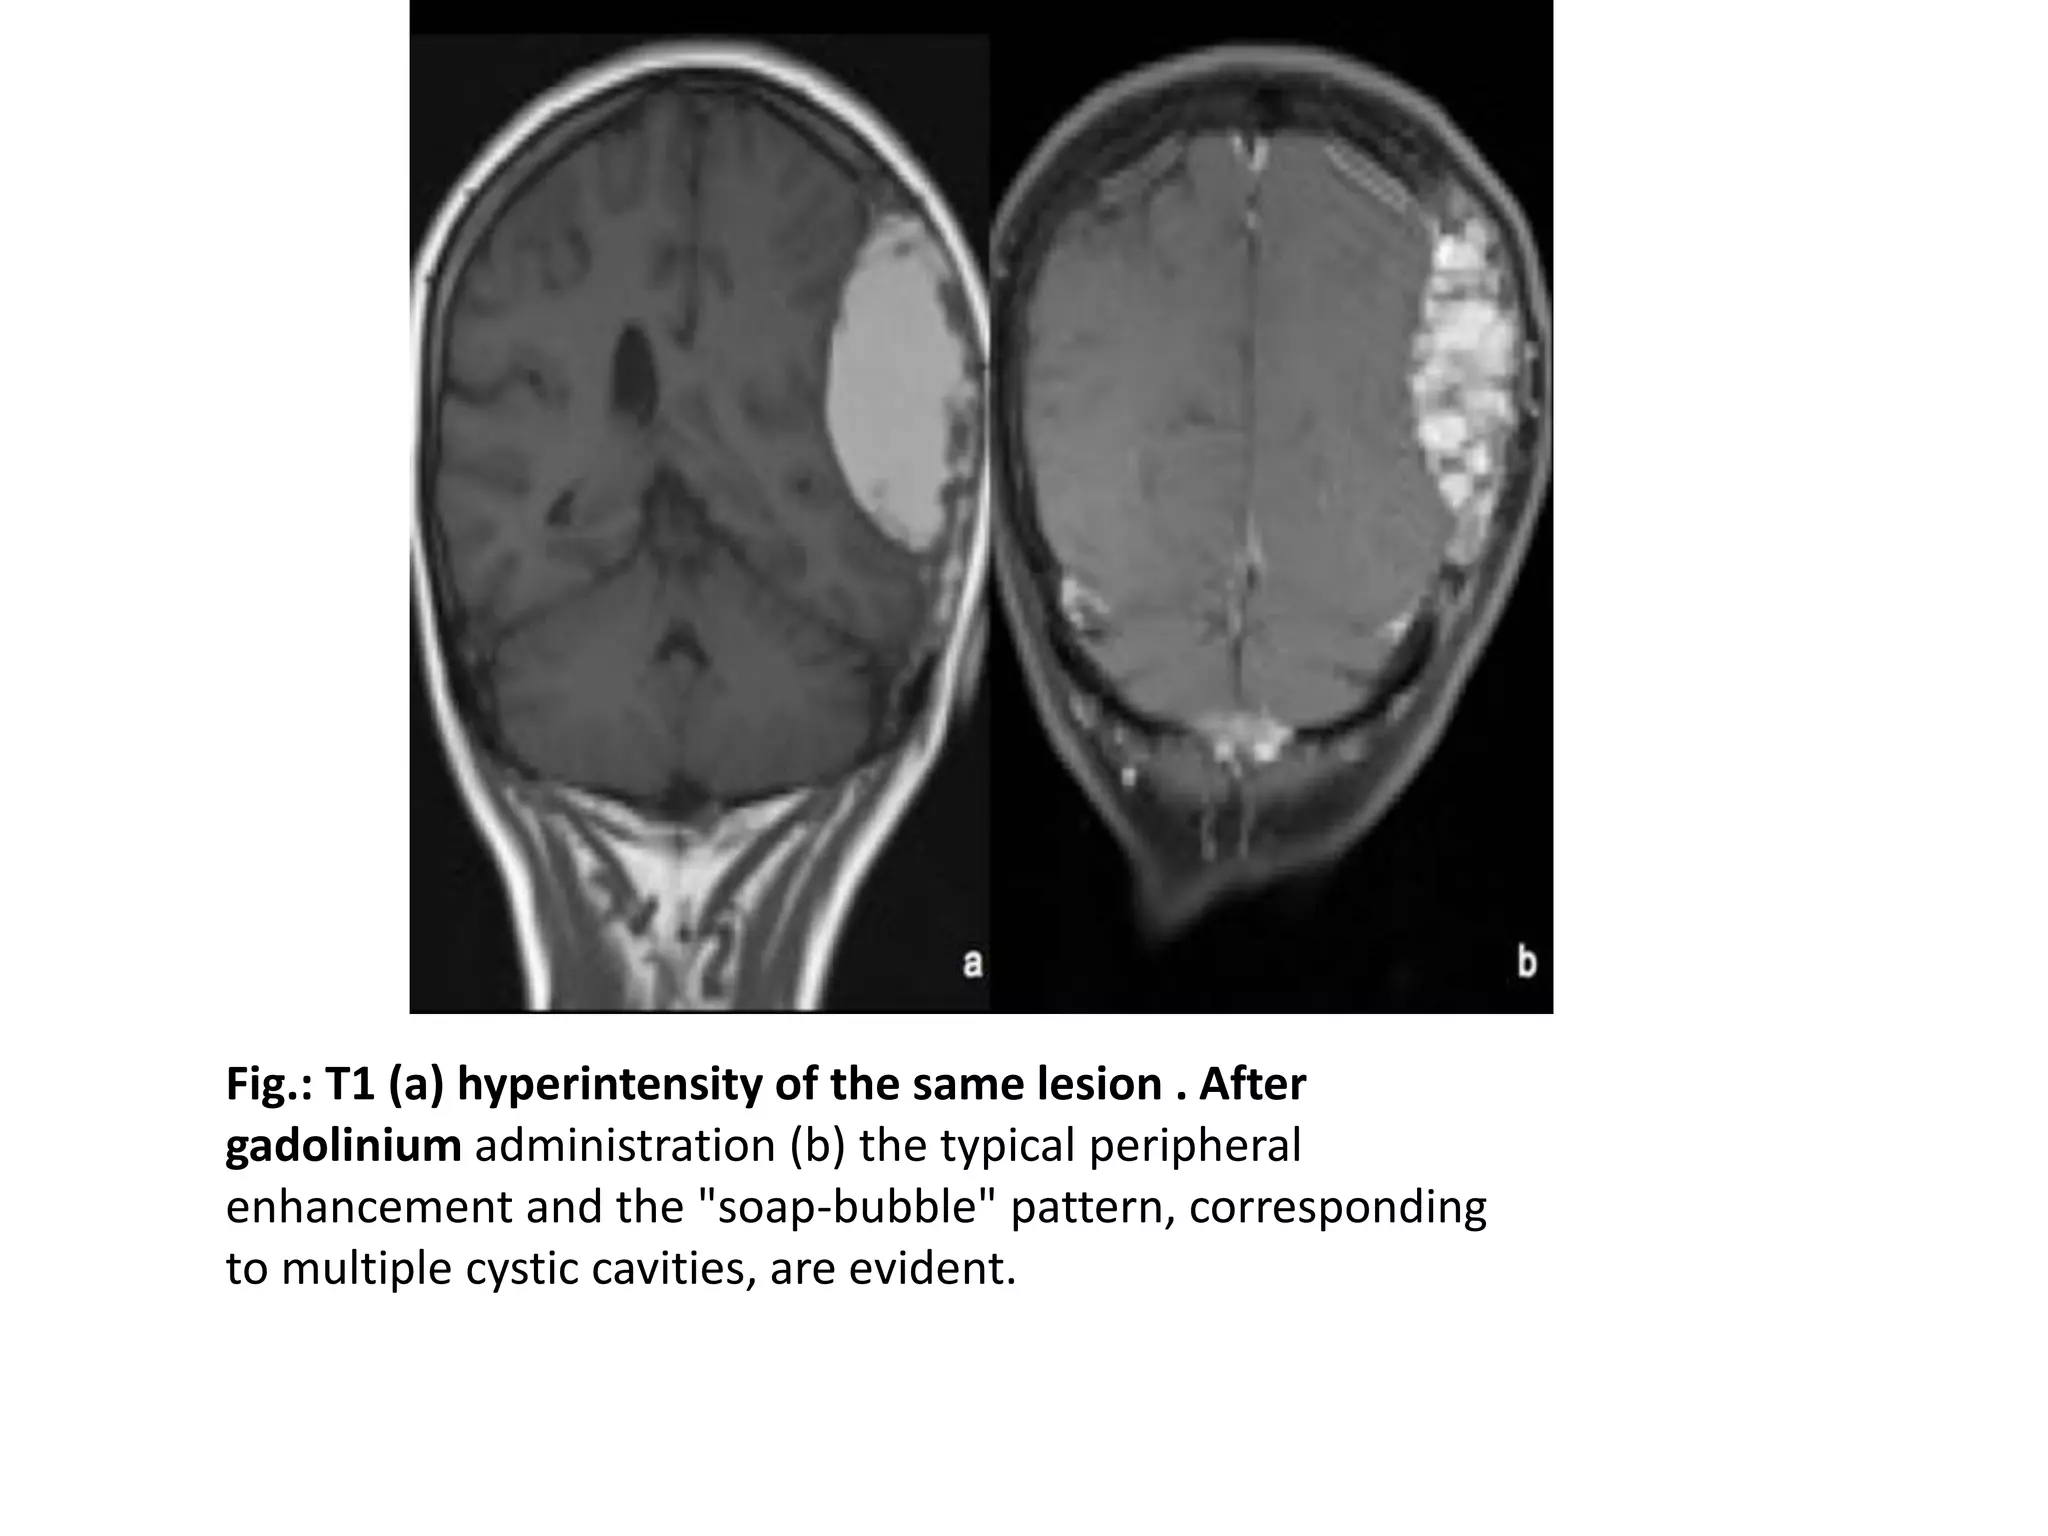

Aneurysmal Bone Cyst

• Aneurysmal bone cysts may occur in any bone, but rarely in

the skull, accounting for only 3-6% of all cases.

• Most are benign but may be locally aggressive.

• Present as painless, progressively rapidly-growing lesion

in childhood and young adulthood

• Characteristic imaging appearance consists of an expanding

osteolytic lesion containing blood-filled spaces of variable

size, frequently with multiple small fluid-fluid levels

representing sedimentation of red blood cells.

• Total excision is the treatment of choice, preoperative

endovascular embolization significantly decreasing

intraoperative bleeding.

Fig.: T1 (a) hyperintensity of the same lesion . After

gadolinium administration (b) the typical peripheral

enhancement and the "soap-bubble" pattern, corresponding

to multiple cystic cavities, are evident.